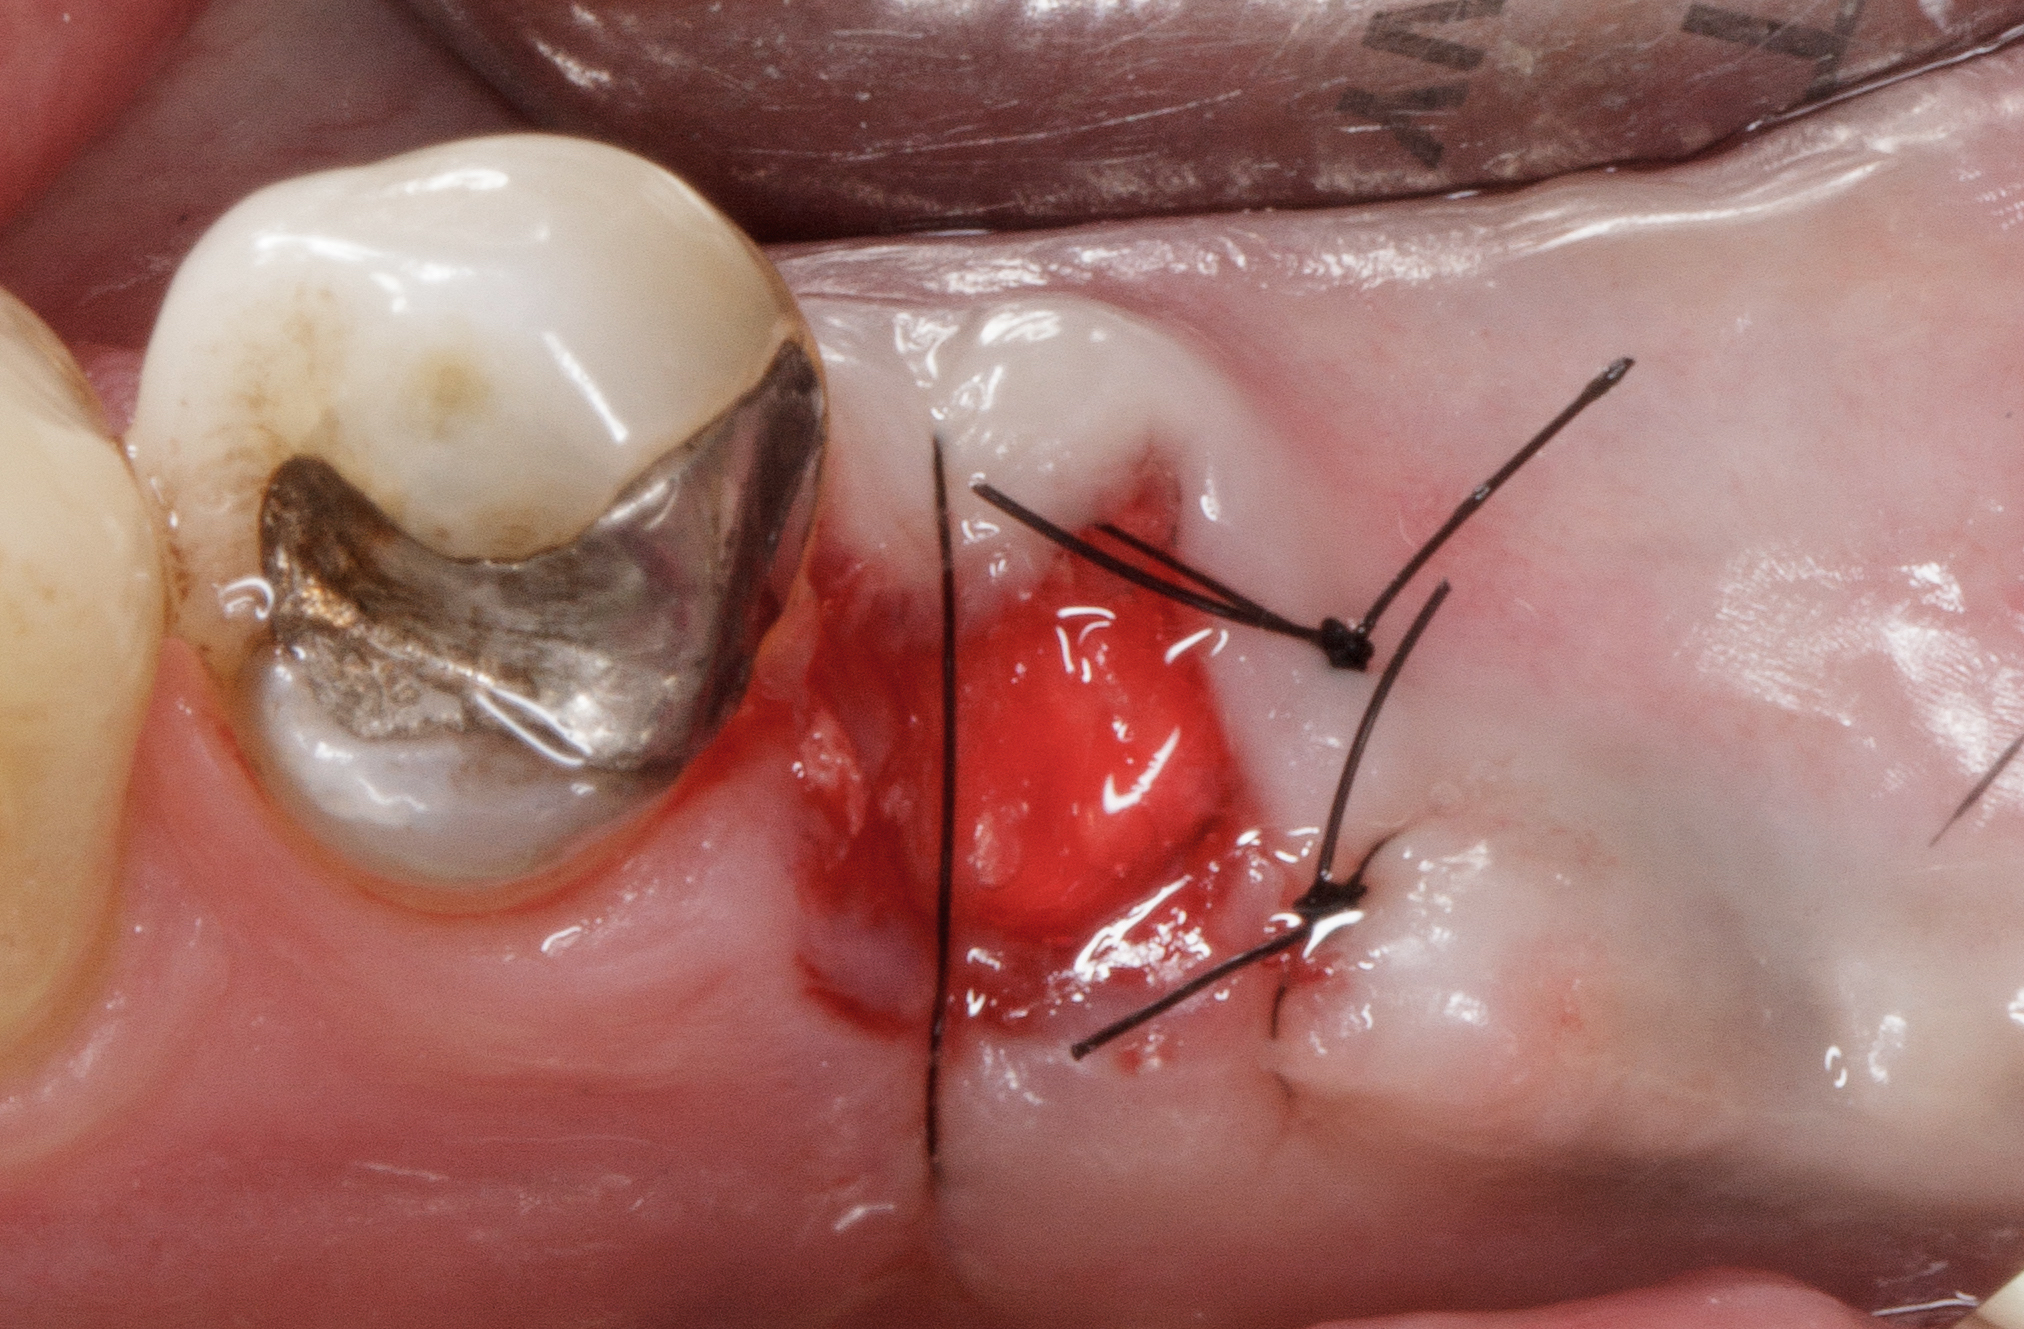

La situazione clinica appare essere la seguente: 4.5 elemento di ponte protesico con 4.6 in estensione, presenza di fistola vestibolare, sondaggio di 7 mm mesiale a radice di 4.5 fratturata con fuoriuscita ematica e purulenta (Figure 3-4).

Si evidenzia chiaramente la frattura radicolare corono-apicale dell'elemento 4.5 (Figure 5-6).

Dopo l’estrazione dentaria si procede a debridement completo dell’alveolo dal tessuto infiammatorio, eseguito solo con strumenti manuali, courettage del margine gengivale con fresa diamantata per rimuovere lo strato epiteliale interno e garantire un maggiore apporto di sangue all’innesto (Figura 7).